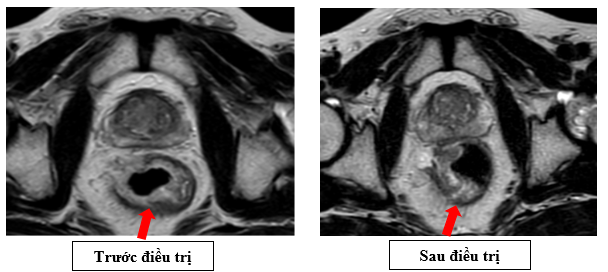

– Cộng hưởng từ vùng tiểu khung (09/2025): Hình ảnh dày không đều thành trực tràng đoạn cách lỗ hậu môn khoảng 3cm, dày lệch phải, dày nhất 11mm, dài khoảng 3mm, không rõ cấu trúc lớp, lớp thanh mạc còn đều, không thâm nhiễm xung quanh.

Hình 4: Bên trái (trước điều trị): khối u thành trực tràng dày, chiếm gần toàn bộ chu vi, lòng trực tràng hẹp rõ, tín hiệu xâm lấn ra ngoài lớp cơ. Bên phải (sau điều trị): khối u kích thước giảm, lòng trực tràng rộng hơn, tín hiệu khối u giảm, ranh giới với lớp mỡ quanh trực tràng rõ hơn -> khối u đáp ứng một phần

Sau 3 tháng điều trị hóa chất tân bổ trợ, bệnh nhân được đánh giá lại:

- Lâm sàng: triệu chứng rối loạn đại tiện cải thiện rõ rệt, không còn tình trạng đi ngoài nhiều lần.

- Nội soi đại trực tràng: so với trước điều trị, khối u thu nhỏ kích thước đáng kể, từ tổn thương sùi loét chiếm gần toàn bộ chu vi trực tràng, sau điều trị lòng trực tràng được mở rộng, ít còn dấu hiệu tắc nghẽn -> phù hợp đáp ứng một phần.

- Cộng hưởng từ tiểu khung: kích thước khối u giảm, mức độ xâm lấn mạc treo trực tràng và khoảng quanh trực tràng thu hẹp, tín hiệu u giảm, xuất hiện nhiều dải xơ hóa

-> Bệnh nhân đạt đáp ứng một phần (PR) trên cả hình ảnh học và nội soi, u trực tràng thu nhỏ rõ rệt,